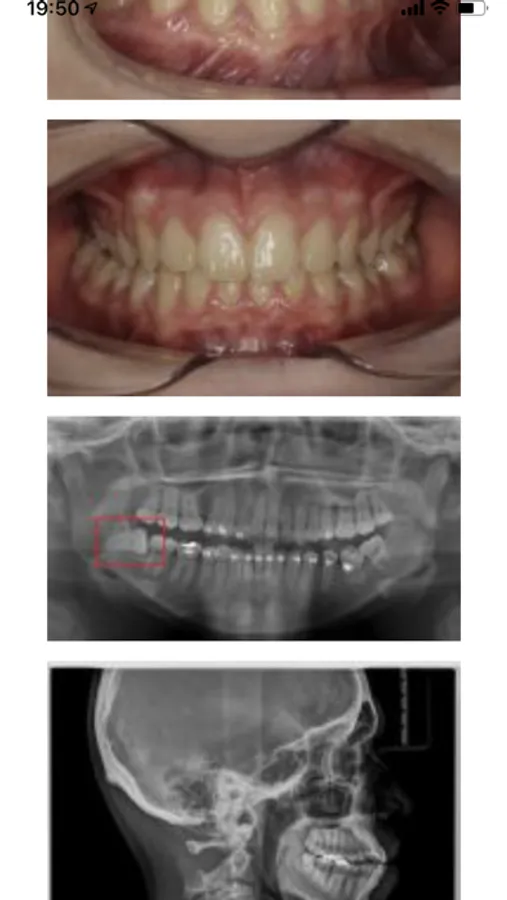

Con esta app podras consultar las citas futuras y pasadas, solicitar citas nuevas, ver los tratamientos realizados, las recetas dispensadas, los presupuestos, las imágenes (fotos, radiografías), los pagos y comunicarte con el personal de la clinica.

Ortodoncia Mercedes Fayos Screenshots